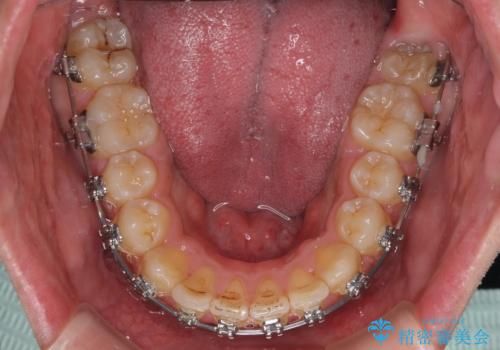

- 矯正装置

- メタルブラケット

- 学生時代に抜歯矯正した歯列が後戻りしてきたとのことで来院された患者様です。

舌の突出癖が原因で上顎前歯が前方に移動したと考えられたため、舌のトレーニングを徹底して行っていただきながら、後戻りを解消していくこととしました。

マウスピース矯正でもワイヤー矯正でも対応可能でしたが、患者様の希望によりワイヤー装置による矯正治療を行うこととしました。

ワイヤー矯正ということで、上顎大臼歯を後方に移動するための補助装置を併用して、積極的に前歯を引っ込めていくこととしました。

上顎歯列全体がスムーズに後方移動でき、1年で治療を終えることができました。